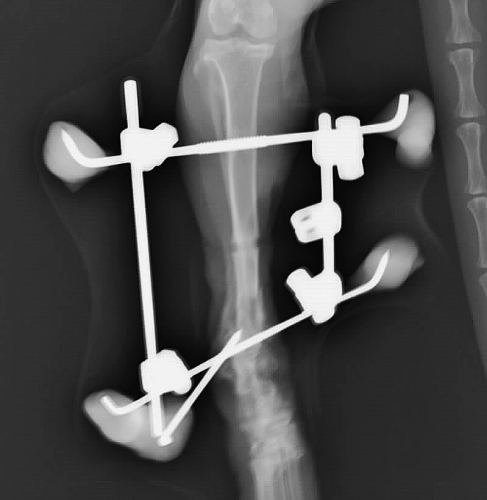

条件が整いましたので、上腕骨骨折、脛骨骨折を2回に分けて整復手術を実施いたしました。上腕骨骨折の説明と経緯は話題が散漫になりますので今回は割愛いたします。脛骨骨折の手術後が下の2枚の写真です。上写真が外観、下がそのレントゲン写真です。

写真をご覧になって、なんだか痛々しそうな、少々大げさな感じを受けた方は多いのではないかと思いますが、こういった骨折の整復手術の方法を「創外固定法」と呼びます。読んで字のごとく「傷の外で固定する方法」です。

この方法は骨に本来かかる様々な力を、骨を貫通する金属ピンを通じて周囲の金属ロッド(写真で棒のように見えるもの)や、レジン(写真で灰色の粘土のように見えるもの)で受けて内部の骨折を外で固定する骨折整復法のひとつです。

オレンジ矢印の部分で骨折端が体外に飛び出しており、廃液(膿などの液体が出ること)しておりましたので、そこにはドレーン(排泄のための管)を設置して、感染の治療を同時に行っていきます。

創外固定法には様々な利点と適用例があるのです。(字数を消費するのでこのコラムでは割愛させていただきますが。)今回この方法を選んだ大きな理由はこの骨折が複合骨折(粉砕骨折)であると同時に特にその一部が、開放骨折(複雑骨折)であったからです。ちょっと面倒な説明ですが、以下をお読みください。

というわけで、今回の脛骨骨折は骨が外に出ている開放骨折、折れた骨がバラバラになっている複合骨折(粉砕骨折)、さらに骨折の場所が遠位端(骨の体から遠い端っこ)と、骨折手術のやり難さと治り難さの悪条件が3拍子揃っていました。こういった場合には創外固定が唯一の選択法になるのではないでしょうか。